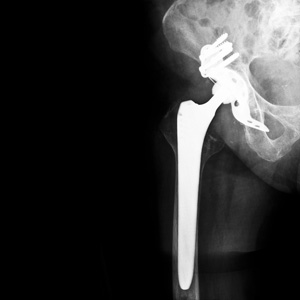

Met het ‘implantatenplan’ wil ze tegemoet komen aan de lacunes die het PIP-schandaal blootlegde. Het is een ambitieus plan dat verder reikt dan enkel borstimplantaten. Ook prothesen (heup, knieën, enkel, discus, enz.), cochleaire implantaten, coronaire stents, pacemakers, hartkleppen, defibrillatoren, endoprothesen, kunstharten en hartmonitors vallen onder de nieuwe regeling.